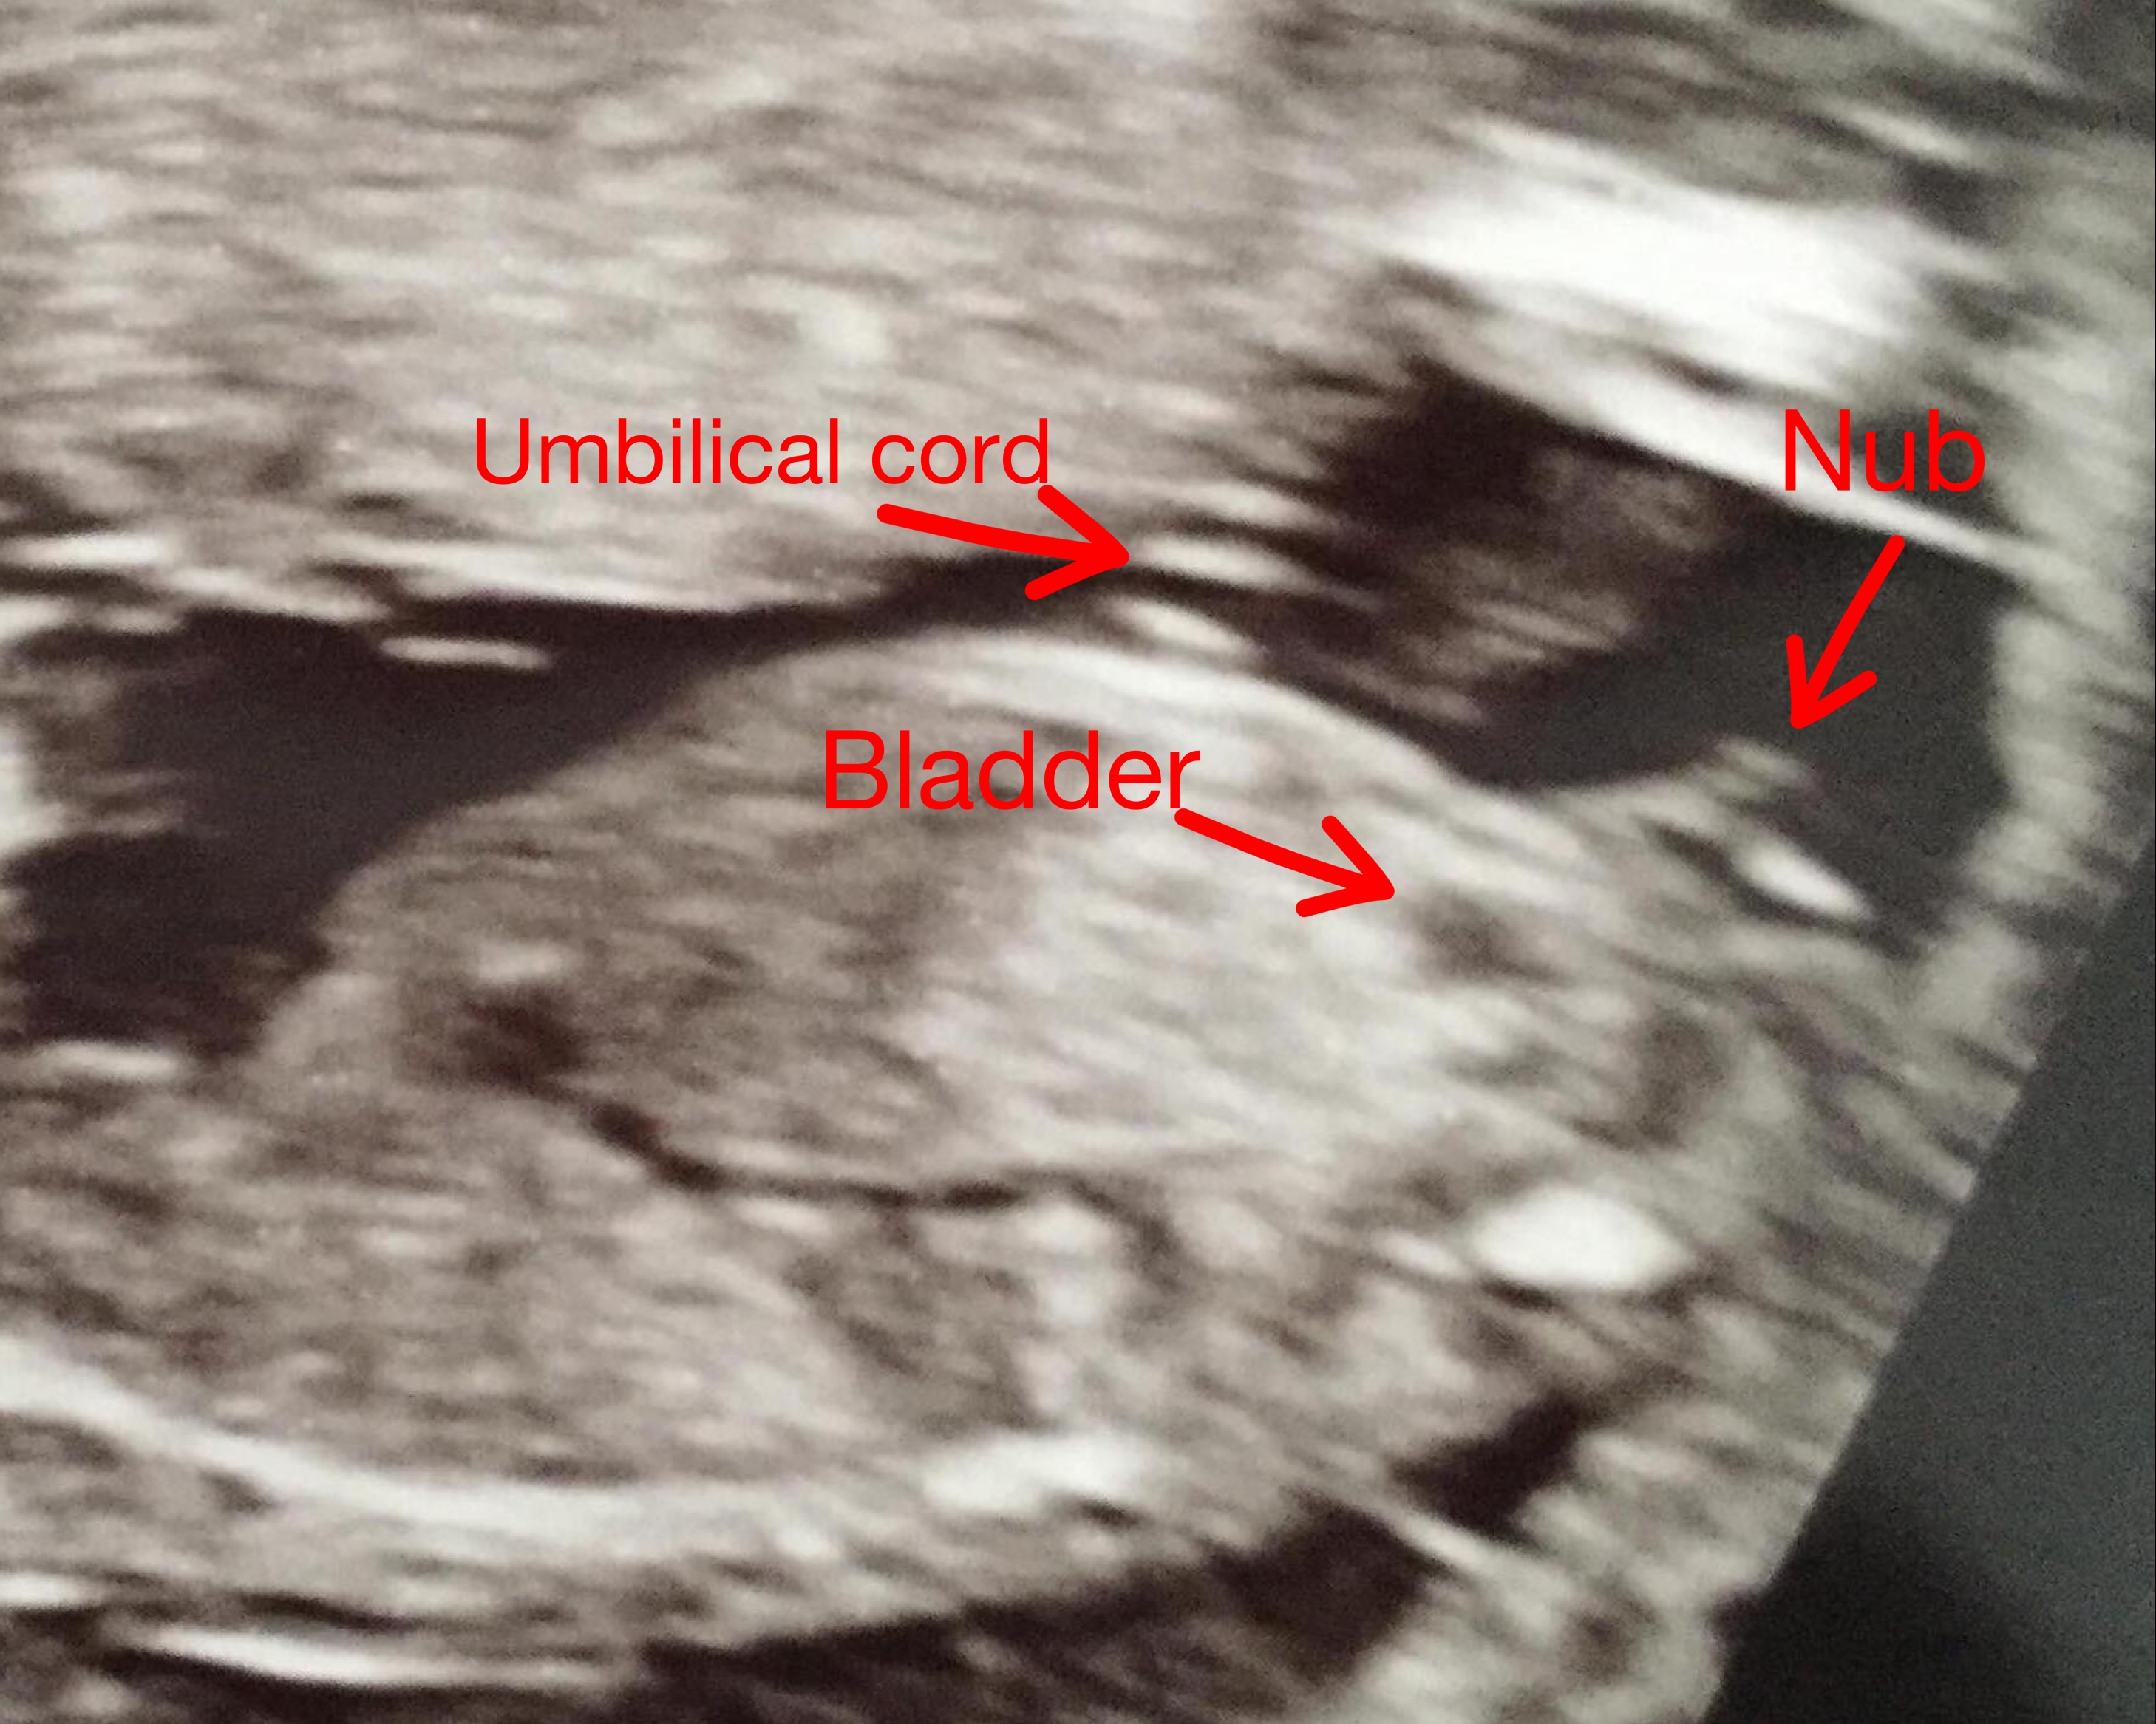

Help me with guesses on this one :) Strange fork that's disconnected and pointing downwards. 13+5 weeks.

Really not the best pic for guessing since baby is upside down but I'll give a slight boy lean. Do you have any other pics?

Upside down? You mean because head is to the right? I have turned it around now if that changes anything. It's lying flat on back.Attachment 38622

I meant it looks like the when the tech took the picture, baby was upside down but I could be wrong. I still think it looks like a boy.

Is it shape of ”the fork” thing at the end that make you say boy or something else? The angle is very parallel to spine but the two (strangly downward pointing) lines at the end really puzzle me.

The nub itself is pointing upwards and is starting to look like a tiny penis. The downward pointing bright line is some other part of the bottom. My two boys looked very similar at that gestation.

So you think the nub is the two small white lines that are all disconnected but not the rest of the structure? Which black area is the bladder? The nub appears to be much to high up if not incl the whole structure